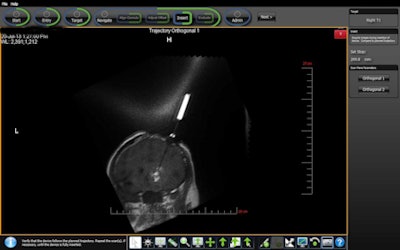

A team from UCSD and Moores Cancer Center used a guidance system called ClearPoint (MRI Interventions) to monitor the delivery and injection of gene therapy in real-time. The researchers injected Toca 511 (vocimagene amiretrorepvec), a novel investigational gene therapy agent, directly into a brain malignancy to make the tumor more susceptible to cancer-killing drugs.

The MRI-guided process provides visual confirmation that the desired amount of drug is delivered into the tumor and gives physicians the ability to make adjustments to optimize the location of drug delivery. The procedure also ensures that Toca 511 is limited to the brain tumor, according to Dr. Clark Chen, PhD, chief of stereotactic and radiosurgery and vice chairman of neurosurgery at UCSD Health System. Tumors light up on MRI during the drug infusion, Chen said.